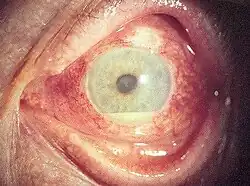

| A person with Behçet's disease exhibiting hypopyon, which can be seen in anterior uveitis | |

Inflammatory eye disease can develop early in the disease course and lead to permanent vision loss in 20 percent of cases. Ocular involvement can be in the form of posterior uveitis, anterior uveitis, or retinal vasculitis. Anterior uveitis presents with painful eyes, conjuctival redness, hypopyon, and decreased visual acuity, while posterior uveitis presents with painless decreased visual acuity and visual field floaters. A rare form of ocular (eye) involvement in this syndrome is retinal vasculitis which presents with painless decrease of vision with the possibility of floaters or visual field defects.[4]